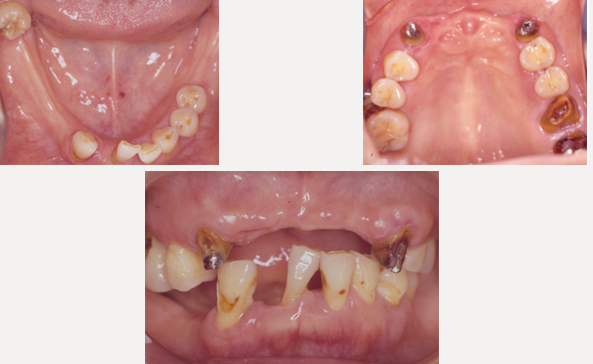

治療前

長い間虫歯、歯周病、欠損部を放置していた為、噛み合わせも含めた総合治療が必要でした。